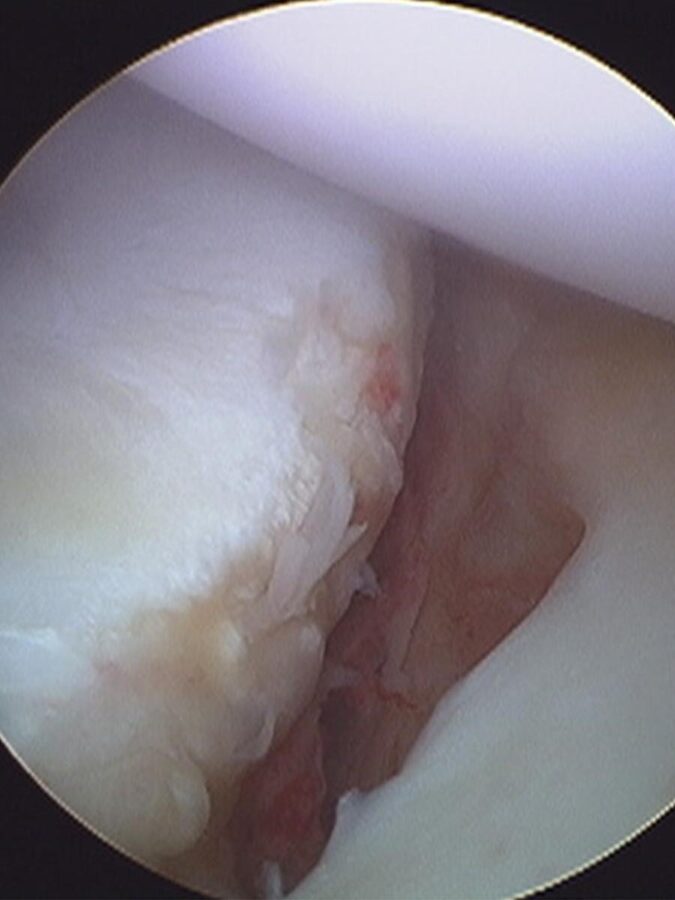

En casi todos los casos la cabeza del humero se sale hacia adelante por un mecanismo de elevación y rotación. La fuerza actuante lleva la cabeza hacia adelante rompiendo los ligamentos, el labrum o fibrocartílago del hombro, fracturando o “abollando” la cabeza del humero (lesión de Hill-Sach). Siempre que el hombro se sale rompe algo…

Desafortunadamente este tipo de lesiones no pueden repararse. El liquido articular que baña la articulación inhibe la cicatrización del labrum, los ligamentos cicatrizan, pero habitualmente estirados y la cabeza no puede “desabollarse”. Por lo que una vez que sucede la luxación existe gran chance de que vuelva a ocurrir con traumas o movimientos mínimos. De acuerdo con las características de la lesión y del paciente (edad, deporte, laxitud articular, antecedentes) se establece la posibilidad de que esto vuelva a pasar. De ahí que se pueda rehabilitar y esperar la evolución o de establecer la necesidad de una intervención.